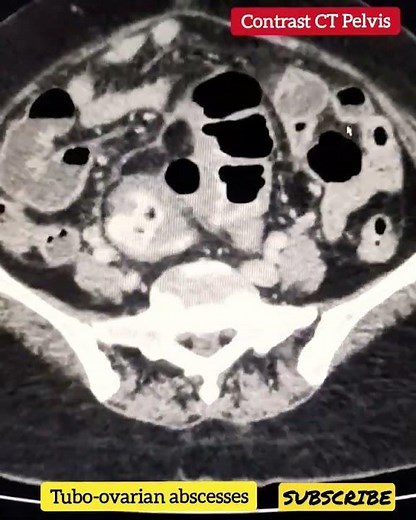

Tubo-ovarian abscesses - Radiology

Basic Radiology